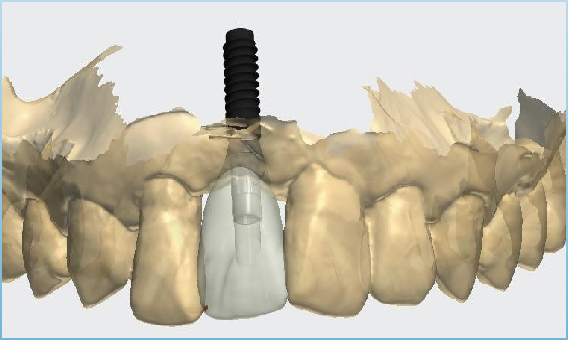

真实案例

TRUE CASE